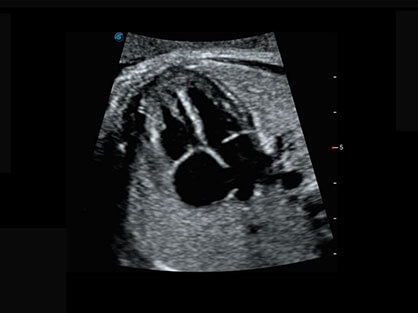

可同时显示组织结构表面和内部的轮廓信息,达到透视效果,为临床提供更丰富的诊断信息。

宽频带腹部凸阵探头和腹部容积探头、大角度腔内探头和腔内容积探头、独特的生殖专用曲柄探头,为妇产应用提供全面诊疗方案。